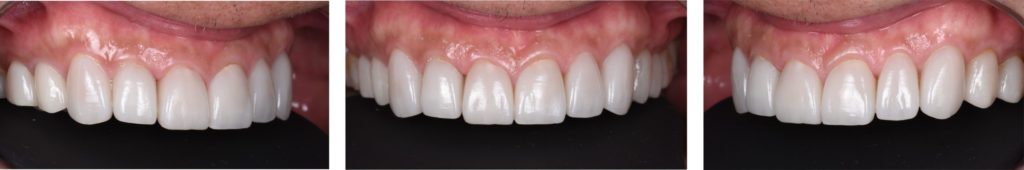

After

術前、術後比較。歯の形態、色調の改善が認められます。